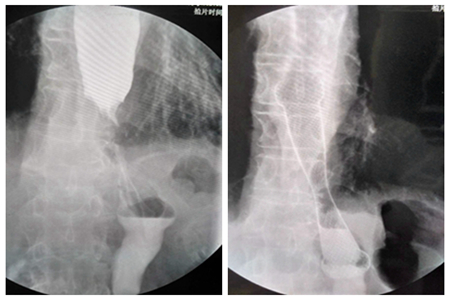

患者3,女,78岁,中段食道癌

放置支架前后对比图

患者4,男,61岁,中下段食道癌